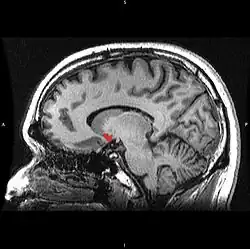

| Прилегающее ядро на МРТ головного мозга человека |

Сенсибилизация — концепция в психологии, объясняющая тот феномен, что люди после повторного приема вызывающего болезненное пристрастие вещества, независимо от вызываемого им чувства удовольствия и часто вопреки пониманию вреда, испытывают ещё большее пристрастие и тягу к повторному потреблению[1][2]. Концепция была предложена на основании опытов, в ходе которых экспериментальным животным вводили психостимуляторы, причём повторное введение лекарства вызывало усиленную психомоторную реакцию на введение прежней дозы[3][4]. Считается, что причина этого явления может быть связана со стойкими изменениями в прилежащем ядре, компоненте так называемого центра удовольствия.

Сенсибилизация — в разной степени выраженный у разных индивидов, специфический в отношении определенного вещества эффект, не связанный с перекрёстными реакциями, хотя она также может быть эффектом многих индуцирующих зависимость лекарств. Этот процесс является противоположностью формированию привыканию (габитуации). Сенсибилизация приводит к снижению чувствительности в области прилежащего ядра. Вследствие этого, ядро может активироваться уже минимальными дозами, а иногда и ассоциированными с наркотиком раздражителями. Так возникает «управляемая влечением» мотивация с импульсивным побуждением к действию. Эта мотивация манифестирует, прежде всего, в таких подкорковых центрах как полосатое тело. Эта так называемая «возбуждающая сенсибилизация» может объяснить феномен, заключающийся в том, что зависимый от какого-либо вещества больной, независимо от субъективного чувства удовольствия, испытывает чувство, вынуждающее снова найти и принять соответствующее наркотическое вещество. При этом данный процесс и следующие за ним действия и поступки в их целенаправленности не воспринимаются больным как насильственные, так как в этом случае не обязательно дело доходит до осознанной непреодолимой потребности в соответствующей субстанции.